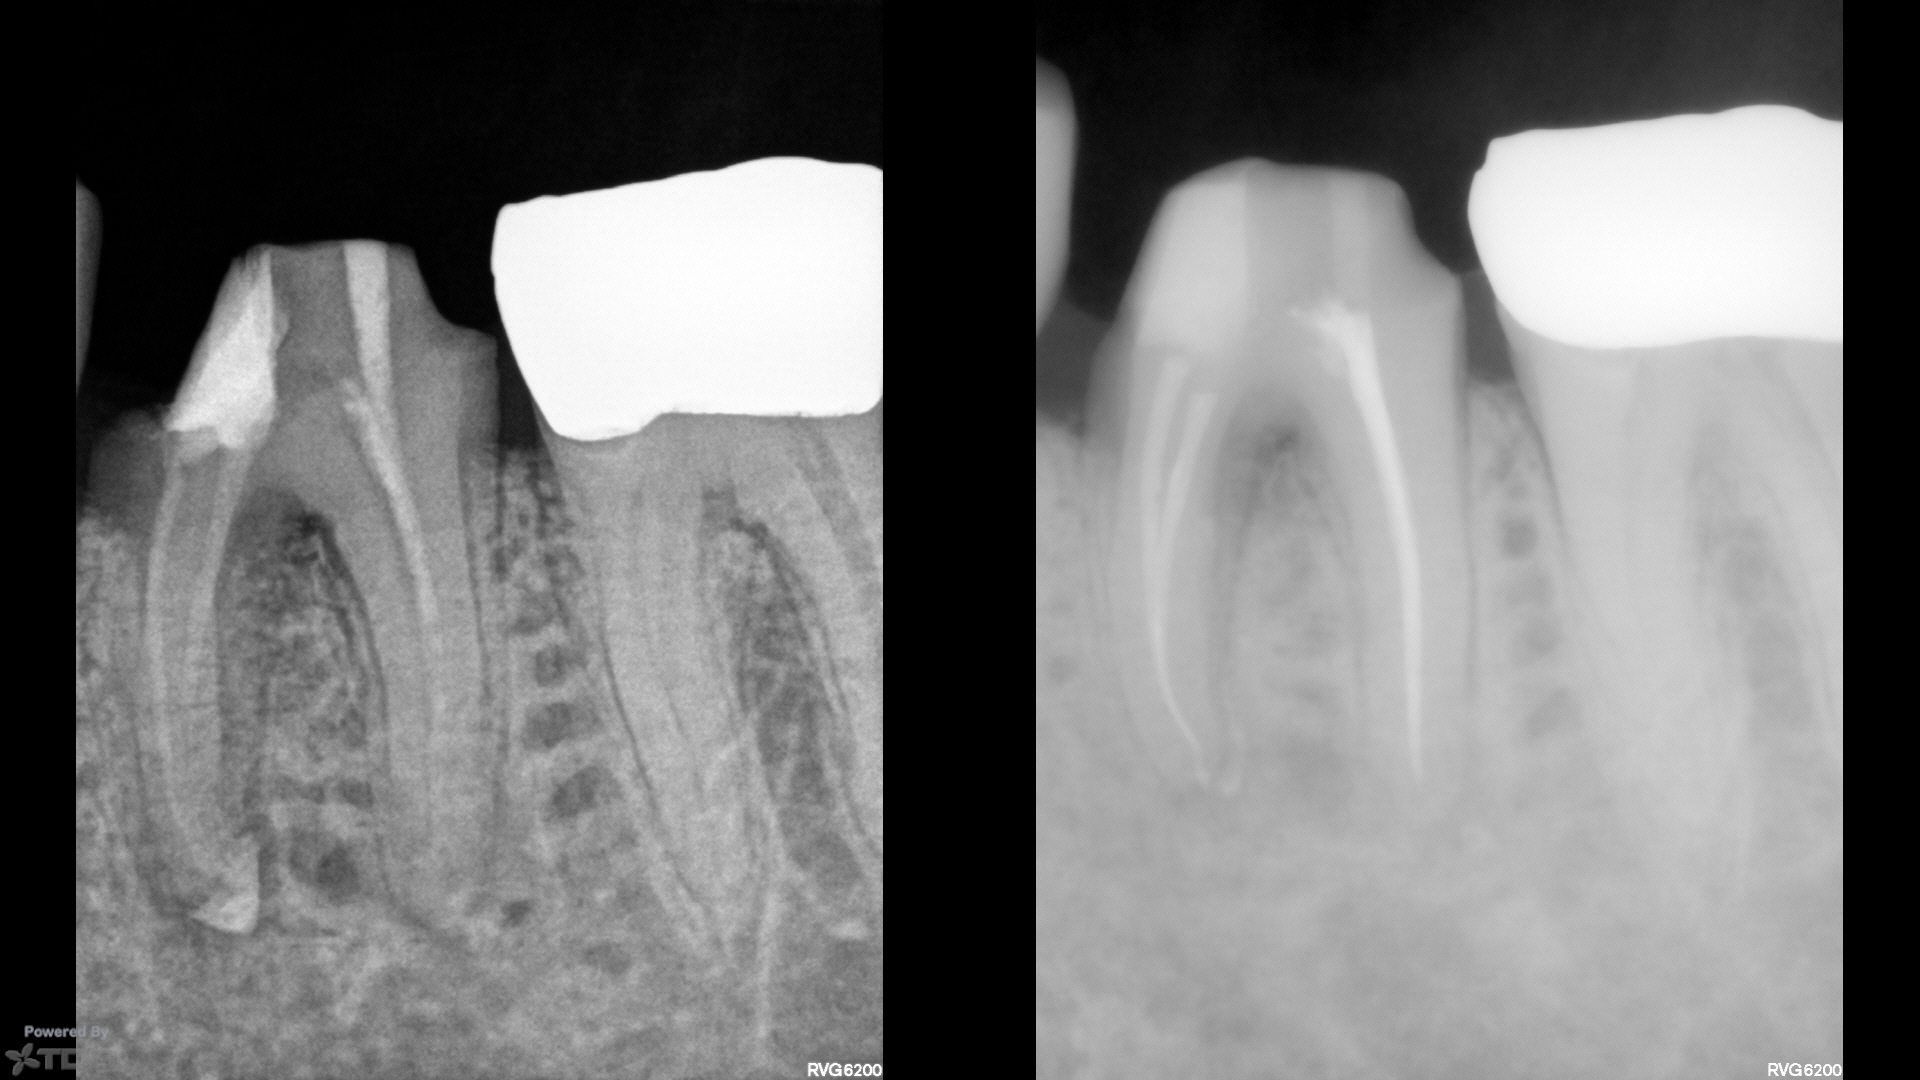

Here, traditional access would have removed most of the remaining PCD. We leveraged the caries and existing loss of tooth structure at the mesial, and poked a hole in the distal with an EG4. Chairside in the scope manages the field and NaOCl irrigation easily.

Temporary was left off with hygiene instructions. Tissue was healing well at 1wk, and was perfect today at 1mo complete (not shown). CBCT at the start visit suggested a missed DB, which was addressed at the complete visit today.

Shapes were SS White V-taper 17/V.04 mesials, 20/V.06 distals.